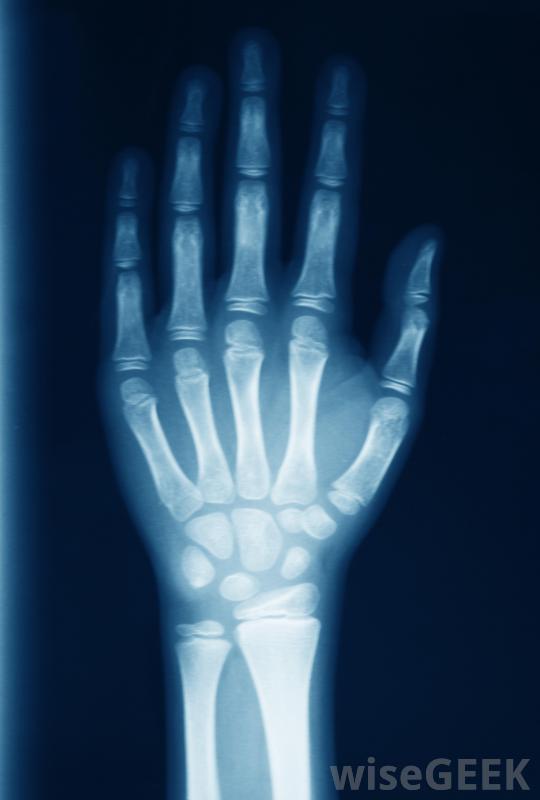

即使您认为脱位并不严重,可以自行愈合,也应立即就医强烈建议避免进一步的永久性损伤。当你治疗拇指脱臼时,医生可能会做的第一件事就是拍x光片,这样他就能看到损伤的程度,包括是否有骨折。脱位可以是简单的,也可以是复杂的。